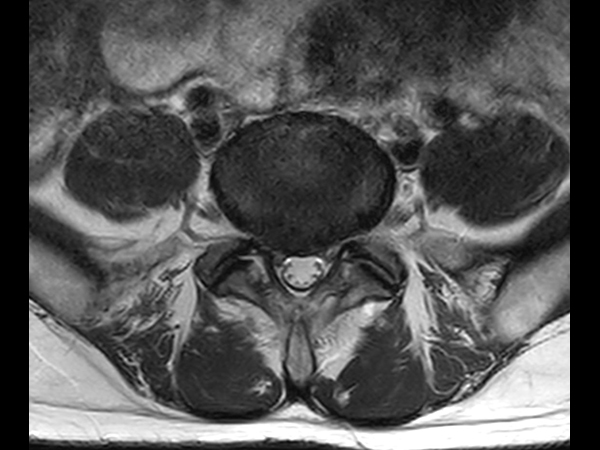

Axial T2w TSE

Axial T1w TSE